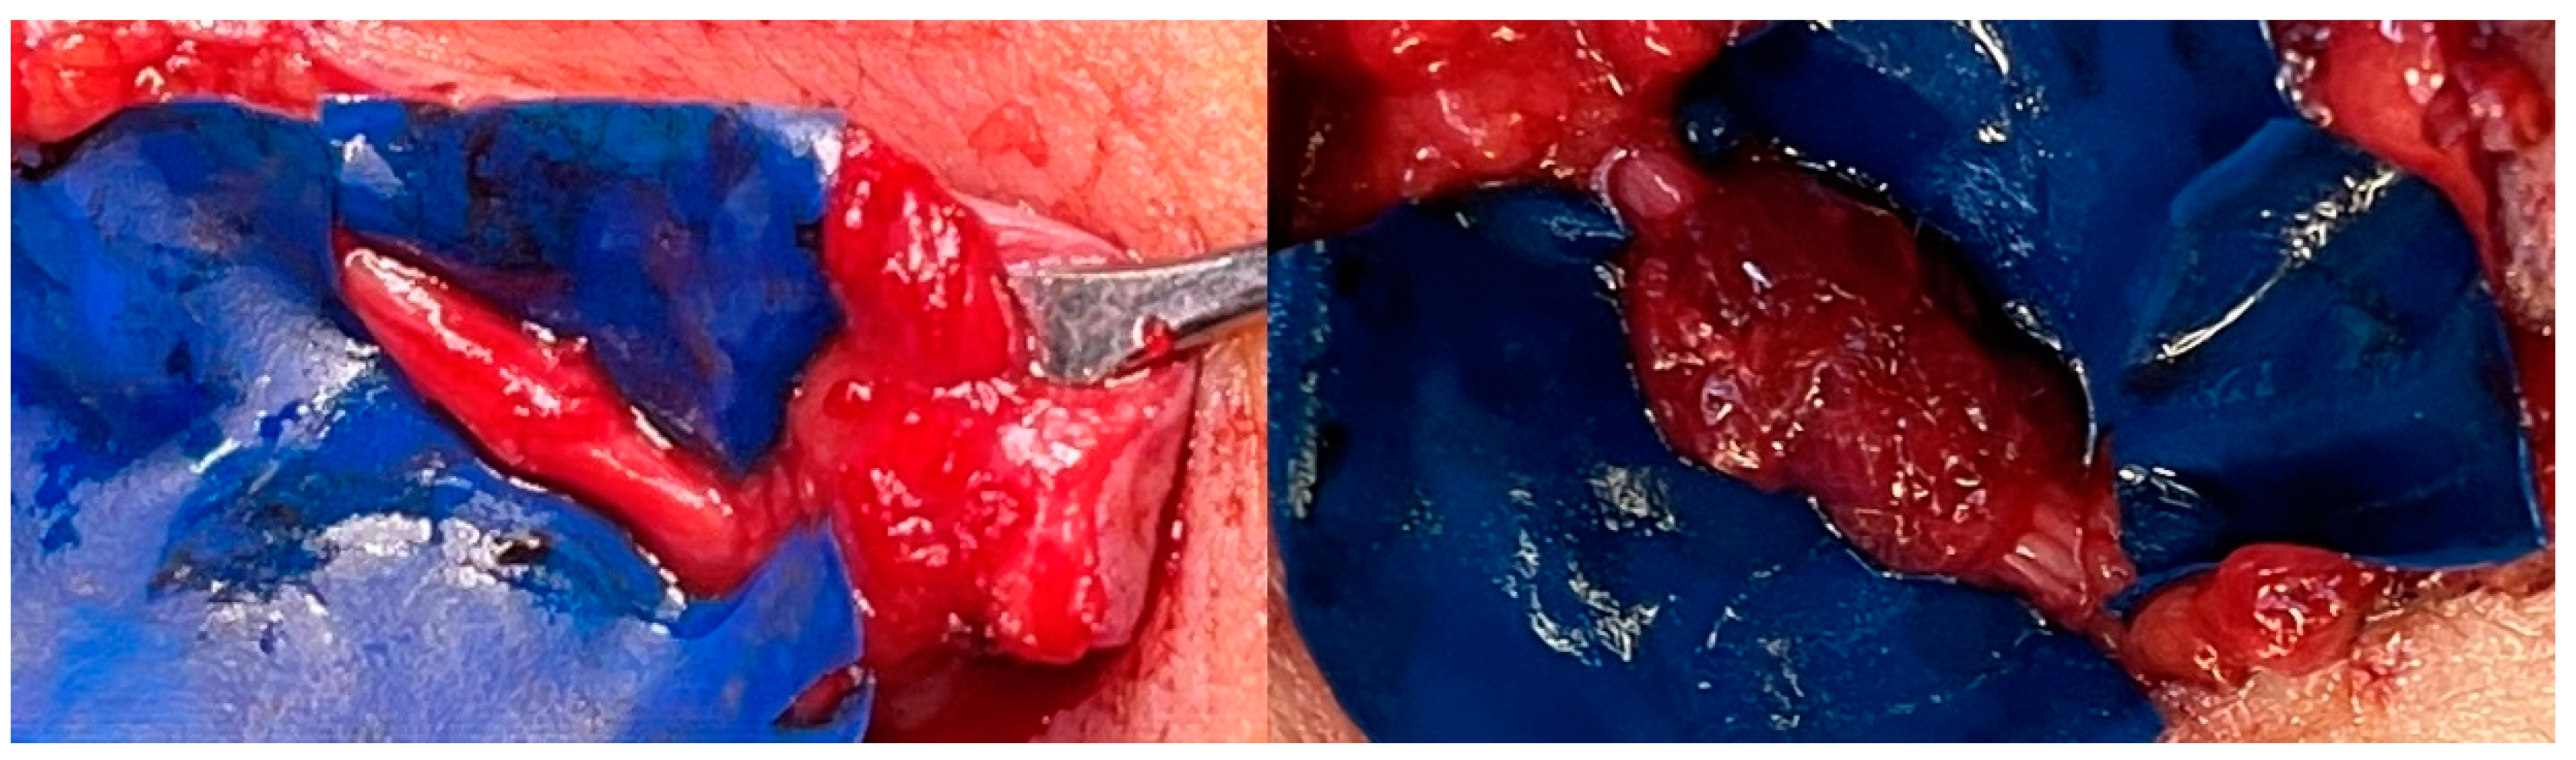

All surgical procedures were performed by plastic surgeons with extensive experience in microsurgery and peripheral nerve surgery, with junior trainees assisting during the procedures. Depending on whether the TSR is performed at the same time as primary amputation of the hand, or secondarily, following the amputation, the skin incision is made on the palm of the hand or at the distal end of the residual limb. In principle, the sensory branches of the median and ulnar nerves must be exposed distally, separated from the motor branch, and dissected in order to perform end-to-end neurorrhaphy with the recipient sensory nerves of the forearm so that the patient becomes able to perceive their entire hand, including fingers (Figure 1A,B).

We performed the operation using general anesthesia, axillary plexus anesthesia, and a tourniquet. Amputation was planned 7 cm proximal to the wrist. After exposing the median and ulnar nerves (Figure 1C), both were separated microsurgically into their two fascicles and branches [21] (Figure 1D). Next, the medial and lateral antebrachial cutaneous nerves were exposed at the elbow. The branches of the median and ulnar nerves were tunneled subcutaneously to the proximal skin incisions below the elbow fold, followed by osteotomy of the ulna and radius 8–9 cm proximal to the wrist. To prevent neuroma of the superficial branch of the radial nerve and the dorsal branch of the ulnar nerve, an end-to-end neurorrhaphy with 9/0 nylon epineural single-button sutures was performed. Alternatively, regenerative peripheral nerve interfaces (RPNIs) could be performed at this point [22]. Once the nerves in the distal forearm had been addressed, the tourniquet was removed. Now the TSR procedure per se continued at the elbow, with a total of three microsurgical nerve coaptations enabling three TSR interfaces (Figure 1E):

For neuroma prevention at the three coaptation sites, RPNIs were wrapped around the coaptation site, harvesting an approximately 2 x 2 cm denervated muscle strip sutured with resorbable 5.0 single-button sutures [22]. Fibrin glue stabilized the construction (Figure 2).

Figure 2. End-to-end re-coaptation and RPNI wrapped around the coaptation site as neuroma prevention.